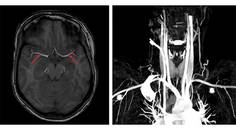

Ischemic Complications from a Facial Lipofilling Procedure

Sanaz Rezaei, MD; Fatemeh Talebi, MDSanaz Rezaei, MD; Fatemeh Talebi, MD - Stroke